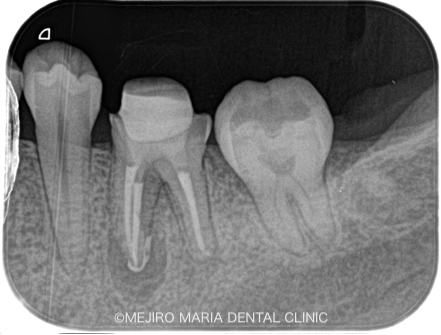

根管治療を2回施し、2回目の治療では、術前に確認されていた瘻孔は消失し、すでに治癒傾向を示していました。

術後3ヶ月で、根尖部に確認されていた黒い透過像(根尖性歯周炎)は明らかな縮小傾向を示していたため、最終補綴(被せ物)の処置を行いました。

今後2年間の経過観察を行い、術後の予後を確認していく予定です。

今回の治療では、大きいスクリュータイプの築造体を除去し、かつ根尖にある破折ファイルを除去したが、レントゲンで分かるのは、健全な歯質をほとんど削らず対処できたことも、今回の症例の重要なポイントであると考えています。